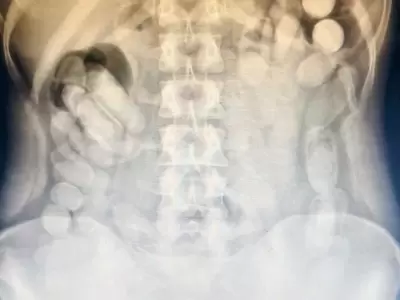

Pero lo peor estaba por revelarse: al ser interrogada, la mujer confesó que había ingerido muchas más. Su cuerpo era, literalmente, una bomba de tiempo. Inmediatamente, el Juzgado Federal Nº 2 de Tucumán ordenó su traslado al Centro de Salud de la capital provincial. La prioridad dejó de ser el delito: se trataba ahora de salvarle la vida. En el nosocomio, una radiografía confirmó el horror: decenas de envoltorios alojados en su abdomen, con el riesgo latente de que alguno se rompiera y provocara una intoxicación letal. La mujer, transformada en "mula humana", ingresó en observación médica estricta.

Horas más tarde, logró evacuar 106 cápsulas adicionales. Sumadas a las 12 incautadas inicialmente, el total alcanzó las 118. El análisis posterior con Narcotest arrojó un resultado contundente: cocaína. El peso final de la sustancia secuestrada fue de 1 kilo 388 gramos. La mujer quedó detenida por orden del magistrado interviniente. Pero, más allá del delito, el caso dejó al descubierto el costado más crudo y peligroso del narcotráfico: el uso de cuerpos humanos como contenedores, la deshumanización, la desesperación y el altísimo riesgo de muerte que asumen muchas veces personas vulnerables en busca de un ingreso.